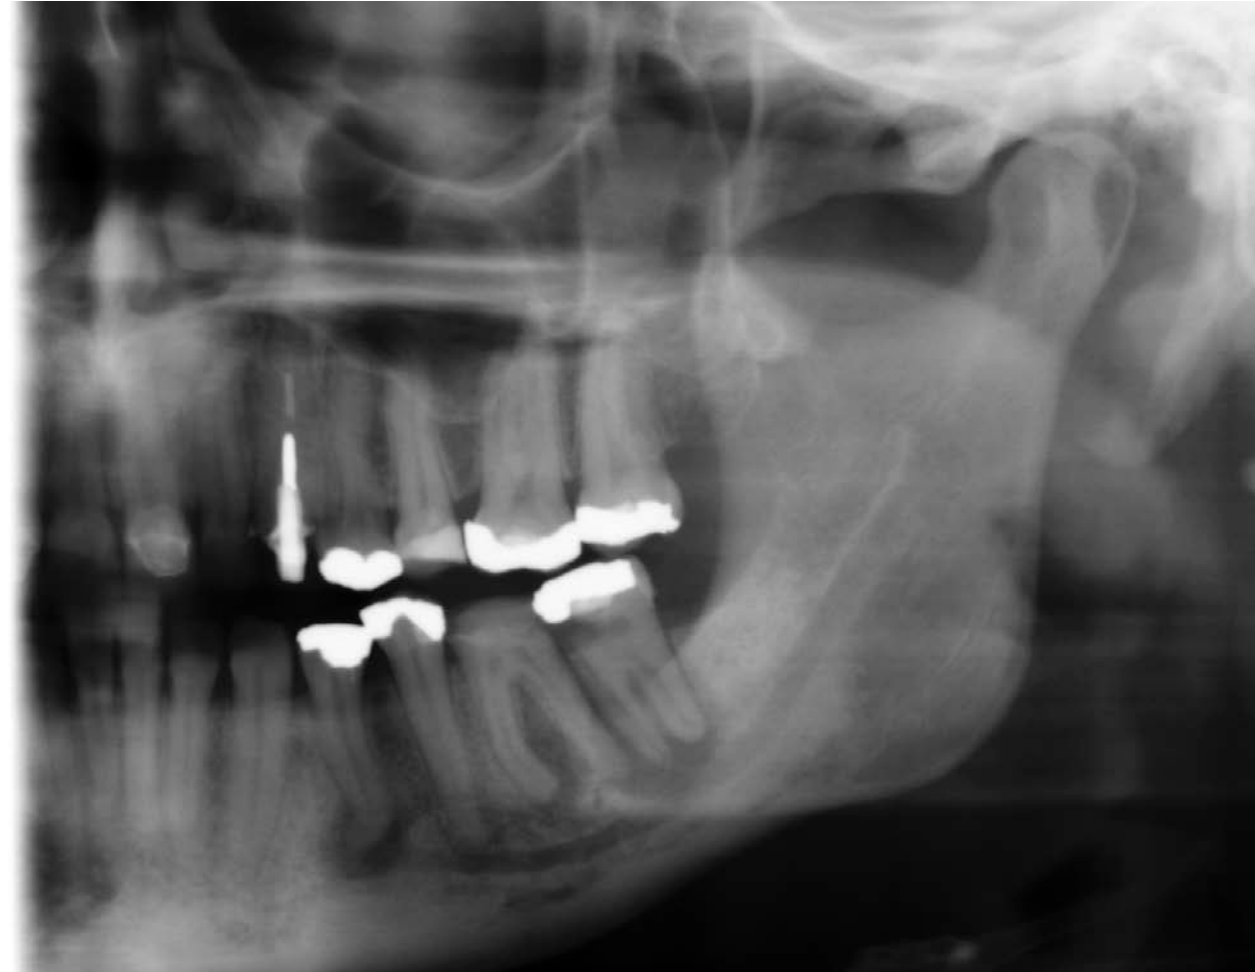

What are Recommended techniques for diagnosing caries?

Bitewings - usually horizontal

Paralleling periapicals

What should we be able to see in radiographs?

When would you use Bitewing Radiograph?